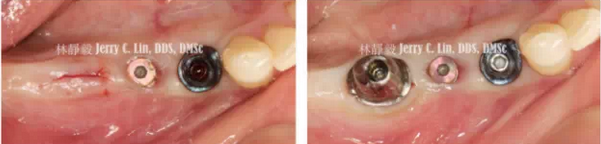

嚴(yán)重種植體周圍炎的處理(二)——林靜毅醫(yī)師